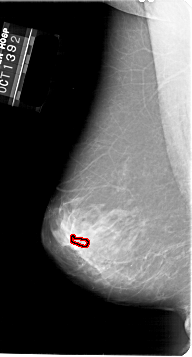

A_1647_1.RIGHT_MLO

RIGHT_MLO LINES 6346 PIXELS_PER_LINE 3301 BITS_PER_PIXEL 12 RESOLUTION 43.5 NON_OVERLAY

FILE: A_1647_1.LEFT_MLO.OVERLAY

TOTAL_ABNORMALITIES 1

ABNORMALITY 1

LESION_TYPE CALCIFICATION TYPE PLEOMORPHIC DISTRIBUTION CLUSTERED

ASSESSMENT 4

SUBTLETY 1

PATHOLOGY BENIGN

TOTAL_OUTLINES 1

BOUNDARY